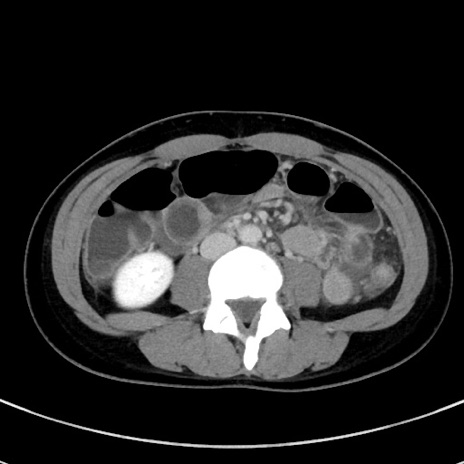

冠状断像

【症例】20歳代女性

【主訴】嘔吐、下腹部痛

【現病歴】昨日夕食後に嘔吐し下腹部痛が出現。本日になっても嘔吐持続し改善しないため来院。

【身体所見】意識清明、BT 37.2℃、BP 108/67mmHg、腹部:平坦、やや硬、下腹部正中から右にかけて圧痛あり、反跳痛軽度あり、tapping pain(+)。

【データ】WBC 13600、CRP 14.94